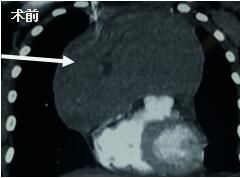

當(dāng)看到病人的CT等外院各項(xiàng)檢查時(shí),我頭皮發(fā)麻,心頭發(fā)怵:巨大的腫塊占據(jù)著整個縱隔,壓迫心臟,與血管關(guān)系密切,初步考慮侵襲性胸腺瘤、胸腺癌或淋巴瘤等,合并腎功能不全,無法完整切除,手術(shù)風(fēng)險(xiǎn)大,手術(shù)并不能提高病人長期生存率,換言之,小伙子等待的是生命的立即終結(jié)。

當(dāng)看到病人癥狀緩解,復(fù)查胸部CT幾近完美,我們那種自豪感油然而生。偶爾去治愈,常常去幫助,總是去安慰,我們深知,小伙子的人生之路并不長,只能深深祈禱他在我們的治療下能走得更遠(yuǎn)一些,能把剩下的日子走的更充實(shí)一些。而我們在能夠幫助人的時(shí)候,別一味地去安慰,永不言棄,是我們這一群胸外人堅(jiān)貞的信念。